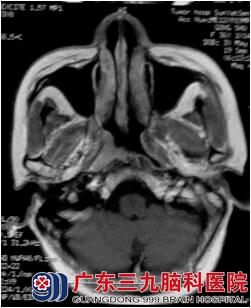

龚小姐于2012年9月因“右颈肿物3年余”,外院活检病理示:鼻咽未分化型非角化性癌。查体:右颈II区淋巴结约26mm X 15mm,边界尚清。9月12日胸部DR未见异常未见骨转移及身体其他部位转移征象,为进一步治疗,于10月份和11月份来广东三九脑科医院肿瘤综合治疗中心行鼻咽癌适形调强放疗,放疗50Gy/25f后复查鼻咽MR示鼻咽病变及颈部淋巴结影基本消失。7000cgy/35f,双颈部放疗5000cgy/25f,右上颈部推量至6000cgy/30f,放疗顺利放疗后行4周期低毒性化疗。

治疗过程很顺利,目前治疗后近2年,复查鼻咽MR:1.鼻咽癌放疗后改变,目前鼻咽部未见明确肿瘤复发征象;2.原右侧颈部颈动脉鞘旁稍大淋巴结已消失。